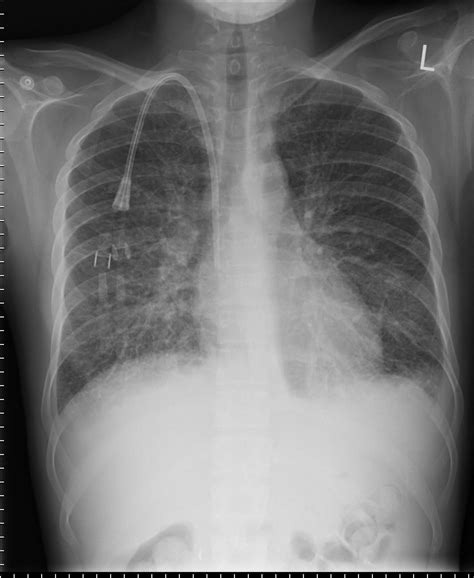

In the field of diagnostic radiology, recognizing specific patterns on a chest X-ray is vital for timely medical intervention. Among the most recognizable and clinically significant findings are Kerley B lines. These thin, short, horizontal lines are frequently identified at the lung periphery and serve as a hallmark indicator of interstitial pulmonary edema. Understanding what these lines signify and how to identify them is essential for healthcare professionals and students alike, as they often provide the first visual clue that a patient is experiencing significant fluid overload, commonly associated with conditions like congestive heart failure.

Kerley B lines are radiographic markers that represent thickened interlobular septa. In a healthy lung, these septa are extremely thin and typically invisible on standard posterior-anterior (PA) chest radiographs. However, when fluid accumulates within these spaces—a condition known as interstitial edema—the septa swell, making them dense enough to be visualized as distinct linear opacities.

These lines are distinct because of their specific orientation and location:

• Appearance: They appear as fine, horizontal, unbranching lines.

• Location: They are found primarily at the lung bases, perpendicular to the pleura.

• Length: They are short, usually measuring less than 2 centimeters in length.

Developing the eye to detect Kerley B lines requires careful inspection of the lung fields, particularly in the costophrenic angles. Because these lines are very thin, they can be easily missed if the image quality is poor or if the exposure is not optimized.

When reviewing a film, look specifically for lines that:

1. Extend all the way to the lateral pleural surface.

2. Are located perpendicular to the pleural line.

3. Do not branch or intersect with other vessels (differentiating them from normal pulmonary vasculature).